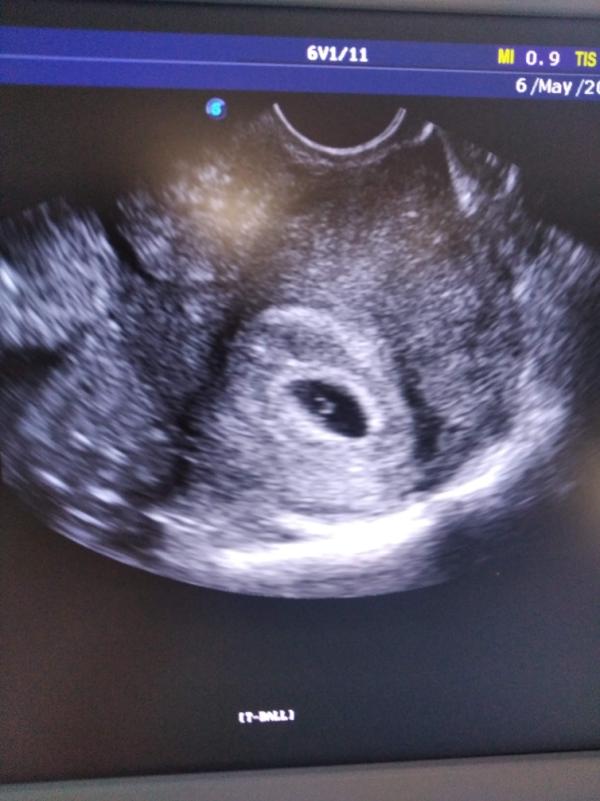

И вот, я мчусь на прием 6 мая 2022 года и...слышу сердцебиение нашей долгожданной малышки...беременность подтвердилась, беременность в матке 5 недель( а это значит всего 4 любовные сцены перед отъездом в отпуск)...стоп-кадр, это как в замедленной съёмке, слезы льются рекой, и гиня плачет...мы два года с ней бок о бок, испробовали возможные варианты, она всегда поддерживала,не сдавалась...муж сдался, у него не было детей, у меня дочь взрослая... я верила, надеялась, ждала, всегда верила, даже когда лишилась одной трубы...